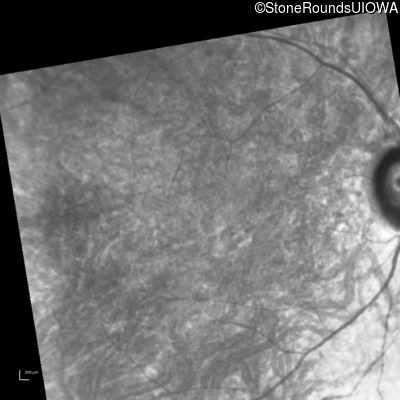

Infrared Fundus Photograph - Left - 20/200 +2

Exemplar